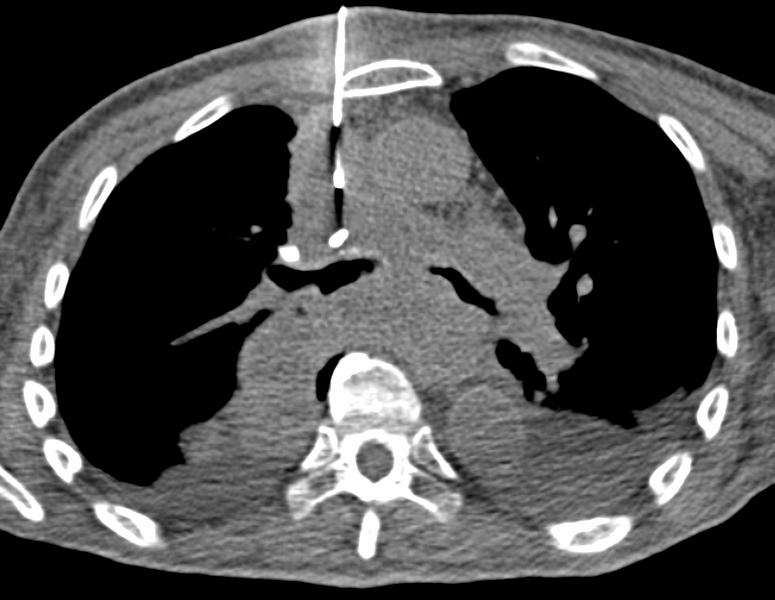

Biopsia de mediastino anterior